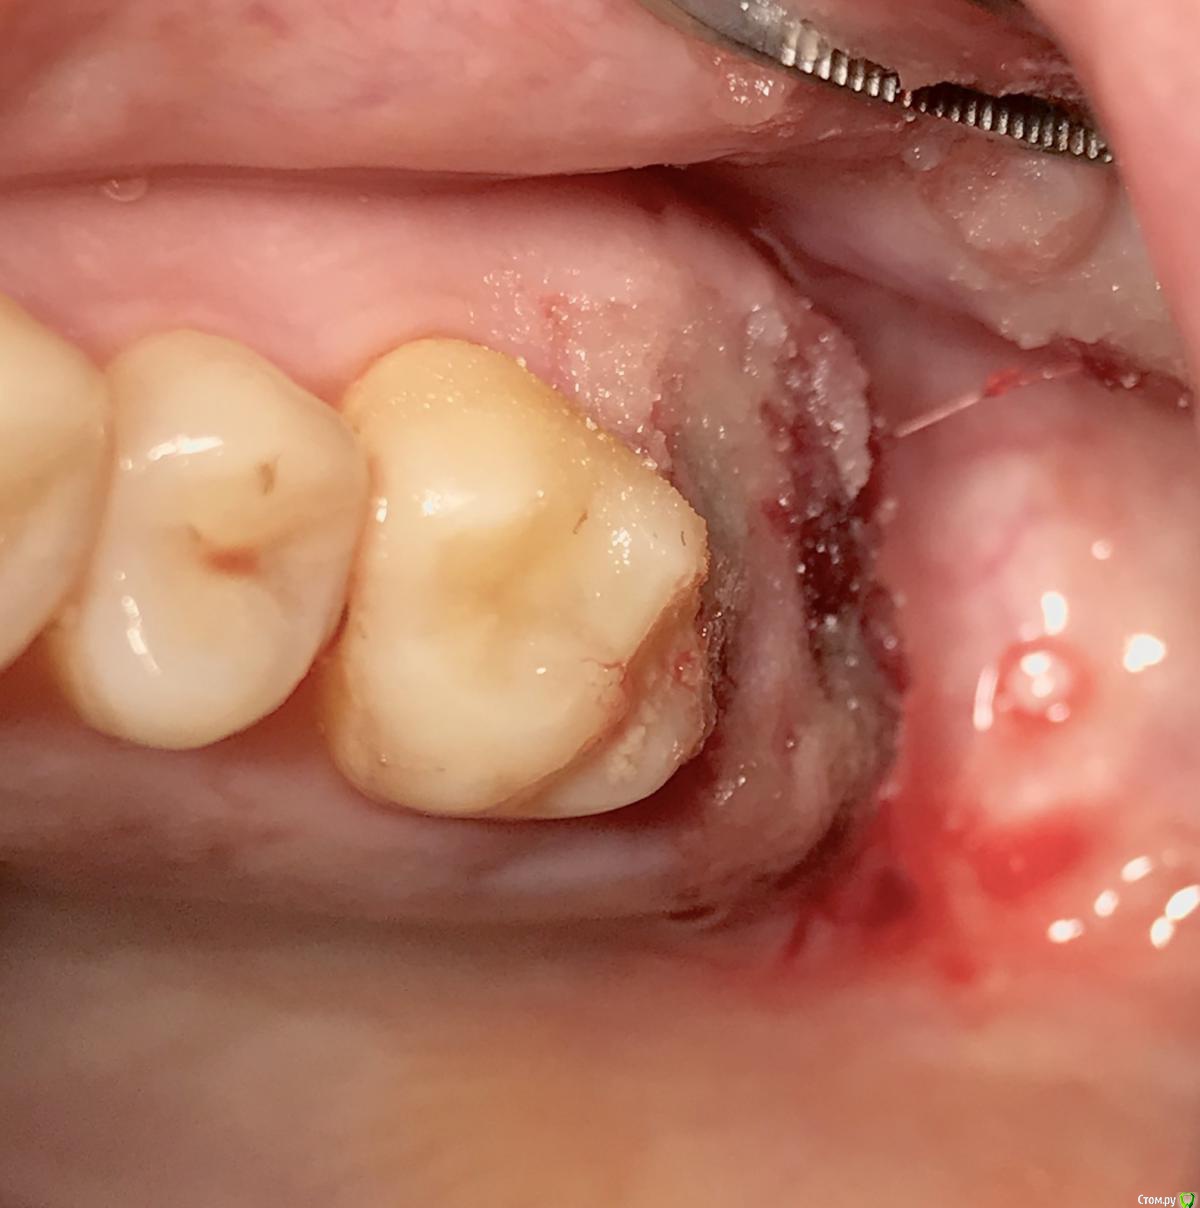

колесников Опубликовано 8 мая, 2017 Поделиться Опубликовано 8 мая, 2017 Немного модифицировал методику Палачи (образование прикреплённой кератинизированой десны междуимплантами,путём выделения и ротирования лоскута с неба). На в/ч у нас обширное поле деятельности со значительными полями кератинизированой слизистой на небе и бугре,что позволяет выделять полосочки не только для пластики в области имплантов,но и для консервации лунки. Можно выделить бугор на питательной ножке и перекинуть его на место 7го. Вариант отсутствует 6ой,присутствует 7ой - выделяем бугор и ведём по маргинальному краю неба у 7го расщепленным разрезом. Длинна может быть значительная,главное свободный конец зафиксировать не в стык а под расщеплённый лоскут принимающего ложа. Одним словом на в/ч с выделением просто. Как быть на н/ч? Обычно только свободный трансплантат с того же неба. Единственный вариант когда можно обойтись местными тканями:отсутствуют нижние 7,8,необходима консервация либо дополнительный объём кератинизированой десны у 7ки. Выделяется с дистального края лунки расщепленная кератинизрованая полоска и далее ведётся по язычному краю лунки . Получаем такую узкую ,но довольно длинную змейку,которую можем зафиксировать медиально, расположив по вестибулярному краю лунки ,либо по язычному ,либо завернуть спиралью. Можно ретромолярно выделить деэпителизированый трансплантат и на подобной змейке перенести его вестибулярно к 7ке. Фото неважные,изначально я не придал значения тому что делаю,позднее результат порадовал объёмом и скоростью регенерации. 1 Ссылка на комментарий

колесников Опубликовано 9 мая, 2017 Автор Поделиться Опубликовано 9 мая, 2017 Да,"приберечь " это про низ. Бугор берётся расщеплённый,не полностью, хорошо регенерирует . Через 4 недели можно брать снова. Травма у нас местно есть в любом случае,кератинизированая расщеплённая десна регенерирует очень хорошо и малоболезненно. Как пример фото разместил :в первом случае со "змейки " я снял швы через неделю и простился,во втором ,где свободный лоскут,остатки его убрал через 3 недели и ещё неделя наблюдений.На фото расщеплённый бугор. На последнем -с выделенным сст. Ссылка на комментарий